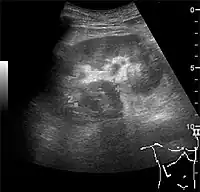

The kidney is divided into parenchyma and renal sinus. The renal sinus is hyperechoic and is composed of calyces, the renal pelvis, fat and the major intrarenal vessels. In the normal kidney, the urinary collecting system in the renal sinus is not visible, but it creates a heteroechoic appearance with the interposed fat and vessels. The parenchyma is more hypoechoic and homogenous and is divided into the outermost cortex and the innermost and slightly less echogenic medullary pyramids. Between the pyramids are the cortical infoldings, called columns of Bertin (Figure 1). In the pediatric patient, it is easier to differentiate the hypoechoic medullar pyramids from the more echogenic peripheral zone of the cortex in the parenchyma rim, as well as the columns of Bertin (Figure 2).[1]

Figure 1. Normal adult kidney. Measurement of kidney length on the US image is illustrated by ‘+’ and a dashed line. *Column of Bertin; ** pyramid; *** cortex; **** sinus.[1]